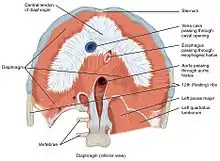

As a dome, the diaphragm has peripheral attachments to structures that make up the abdominal and chest walls. The muscle fibres from these attachments converge in a central tendon, which forms the crest of the dome.[7] Its peripheral part consists of muscular fibers that take origin from the circumference of the inferior thoracic aperture and converge to be inserted into a central tendon.

The muscle fibres of the diaphragm radiate outward from the central tendon. While the diaphragm is one muscle, it is composed of two distinct muscle regions: the costal, which serves as the driver in the work of breathing, and crural diaphragm, which serves as an "anchor;" attaching the muscle to the lower ribs and lumbar vertebrae. The costal diaphragm is further divided into ventral, medial, and dorsal costal portions. [8][9]

The vertebral part of the diaphragm arises from the crura and arcuate ligaments. Right crus arises from L1-L3 vertebral bodies and their intervertebral discs. Smaller left crus arises from L1, L2 vertebral bodies and their intervertebral discs.[8][7][10] Medial arcuate ligament arises from the fascia thickening from body of L2 vertebrae to transverse process of L1 vertebrae, crossing over the body of the psoas major muscle. The lateral arcuate ligament arises from the transverse process of L1 vertebrae and is attached laterally to the 12th rib. The lateral arcuate ligament also arises from fascia thickening that covers the quadratus lumborum muscle. The median arcuate ligament arises from the fibrous parts of right and left crura where descending thoracic aorta passes behind it. No diaphramatic muscle arises from the median arcuate ligament.[8] Both adrenal glands lie near the diaphragmatic crus and arcuate ligament.[11]

The costal part of diaphragm arises from the lower four ribs (7 to 10) costal cartilages.[8]

The central tendon of the diaphragm is a thin but strong aponeurosis near the center of the vault formed by the muscle, closer to the front than to the back of the thorax. The central part of the tendon is attached above to pericardium. The both sides of the posterior fibres are attached to paracolic gutters (the curving of ribs before attaching to both sides of the vertebral bodies).[8]

There are a number of openings in the diaphragm through which structures pass between the thorax and abdomen. There are three large openings — one for the aorta (aortic hiatus),[3] one for the esophagus (esophageal hiatus), and one for the inferior vena cava (the caval opening),[8] as well as a series of smaller openings.[12][13]

The inferior vena cava passes through the caval opening, a quadrilateral opening at the junction of the right and middle leaflets of the central tendon, so that its margins are tendinous. Surrounded by tendons, the opening is stretched open every time inspiration occurs. However, there has been argument that the caval opening actually constricts during inspiration. Since thoracic pressure decreases upon inspiration and draws the caval blood upwards toward the right atrium, increasing the size of the opening allows more blood to return to the heart, maximizing the efficacy of lowered thoracic pressure returning blood to the heart. The aorta does not pierce the diaphragm but rather passes behind it in between the left and right crus.

There are several structures that pierce through the diaphragm, including: left phrenic nerve pierces through the central tendon, greater, lesser, and least thoracic splanchnic nerves pierces through bilateral crura, and lymphatic vessels that pierce throughout the diaphragam, especially behind the diaphragm.[8]